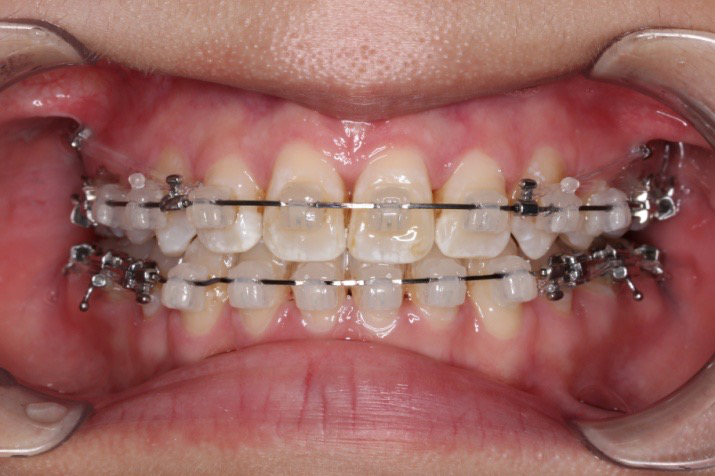

2018.11.14  术后磨牙尖牙I类关系,中线齐,覆合,覆盖正常

2019.08.06  术后  10个月复查

迷你观评价:上下牙齿中线与面中线对齐,笑弧协调,微笑时牙龈暴露量正常,微笑时横向正常,左右唇基本对称。

微观评价:牙齿整齐,咬合关系良好,上下前牙转矩及突度控制良好,磨牙关系I类,尖窝咬合关系良好,OB,OJ正常。